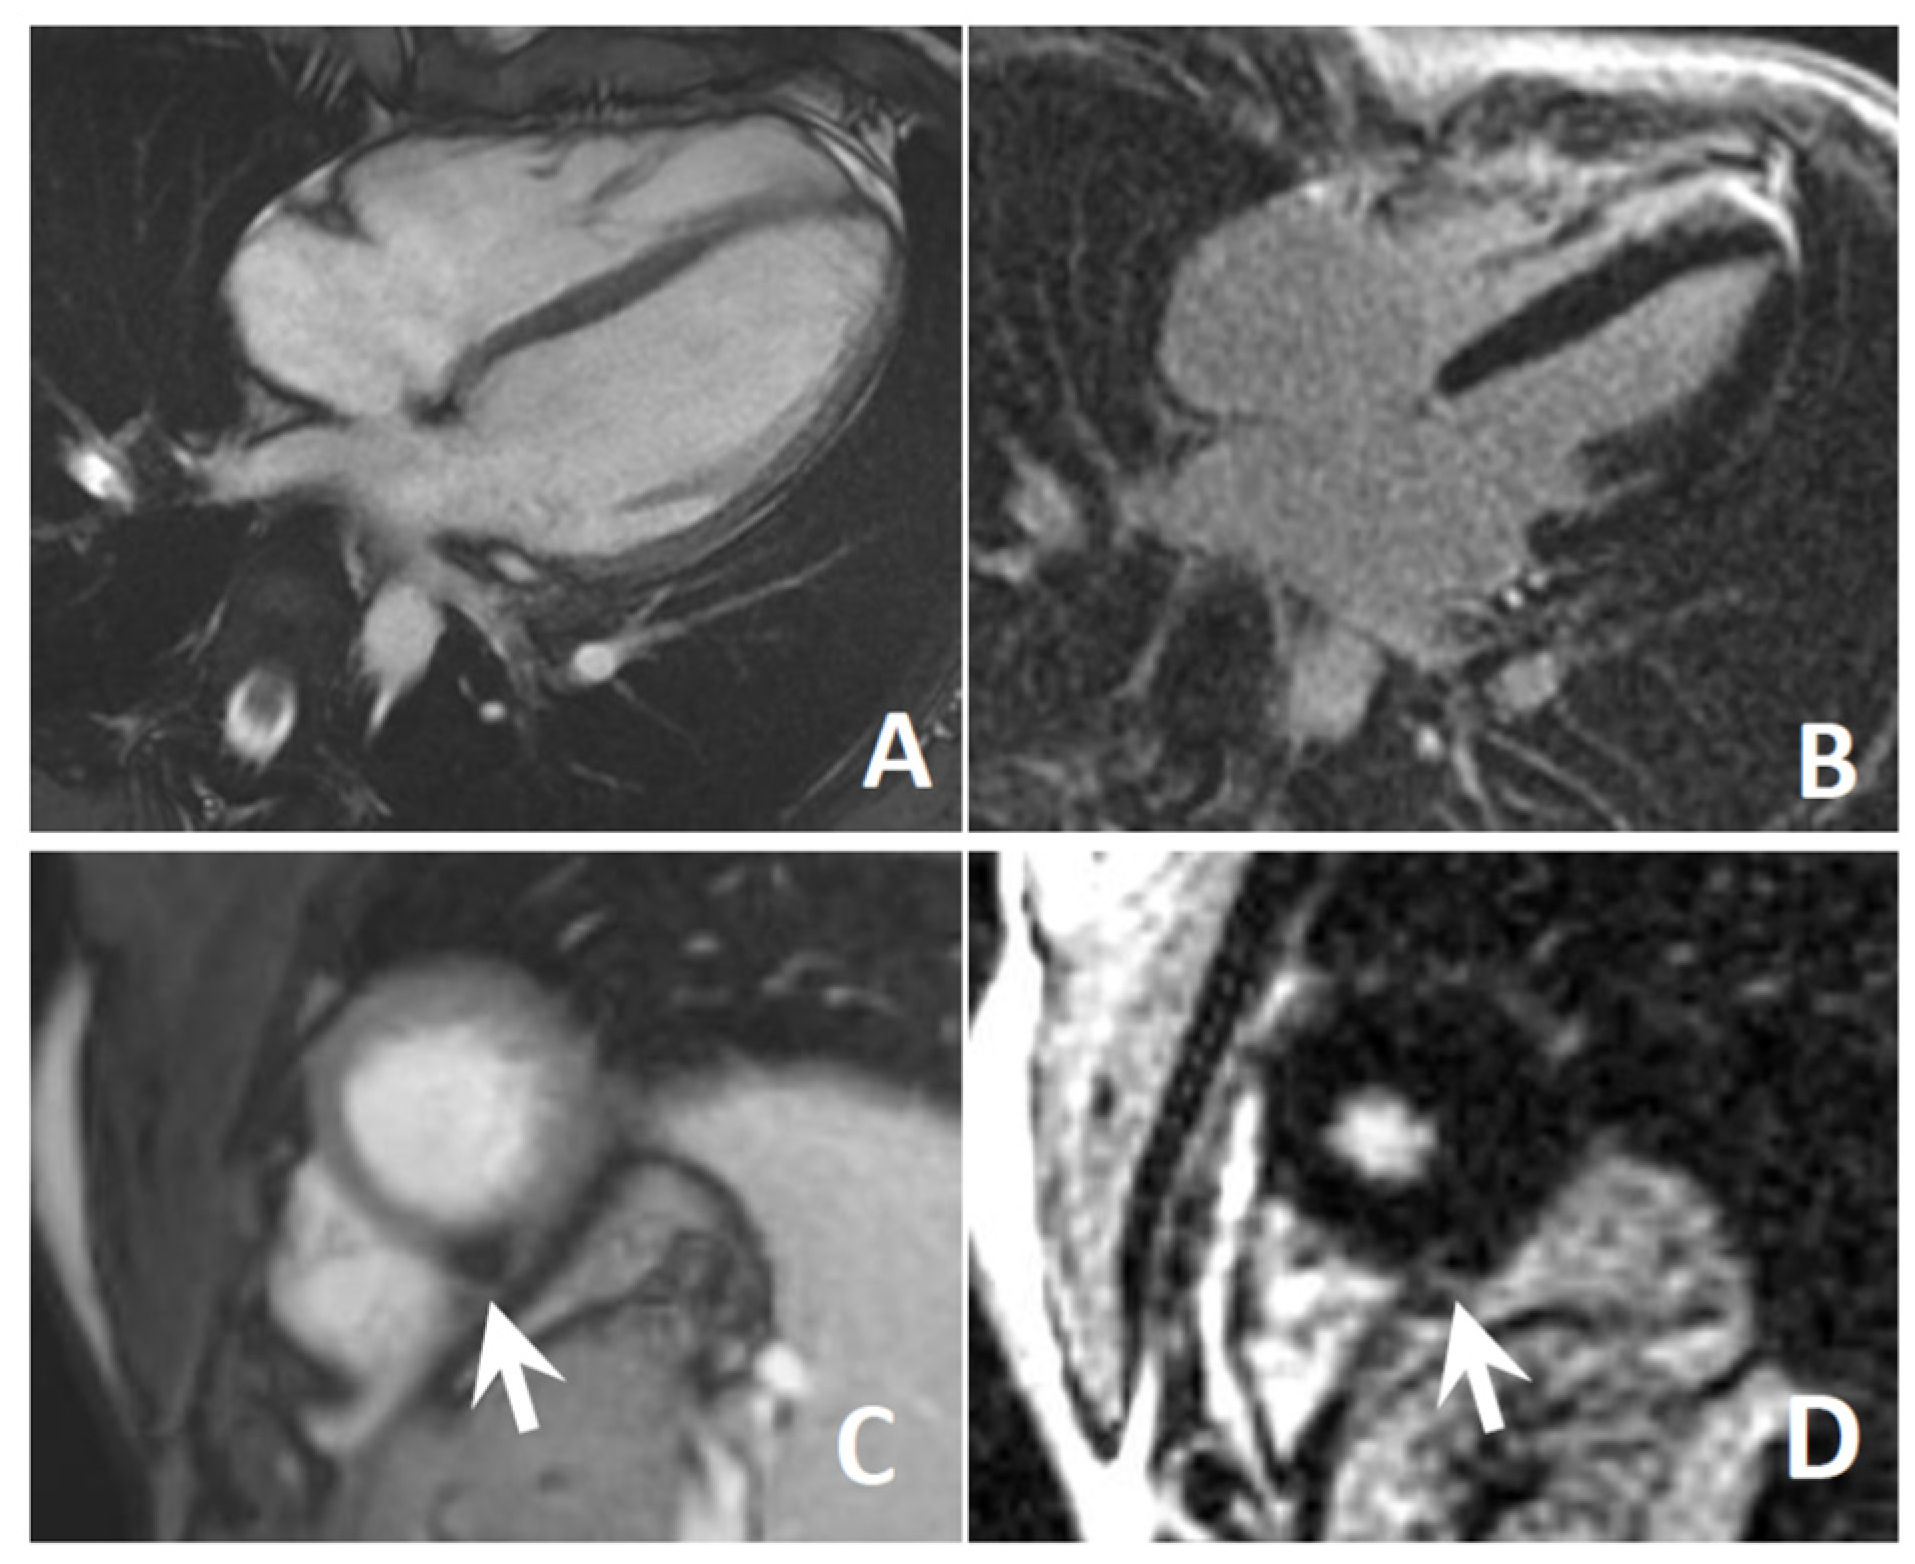

3.4. Cardiological Assessment